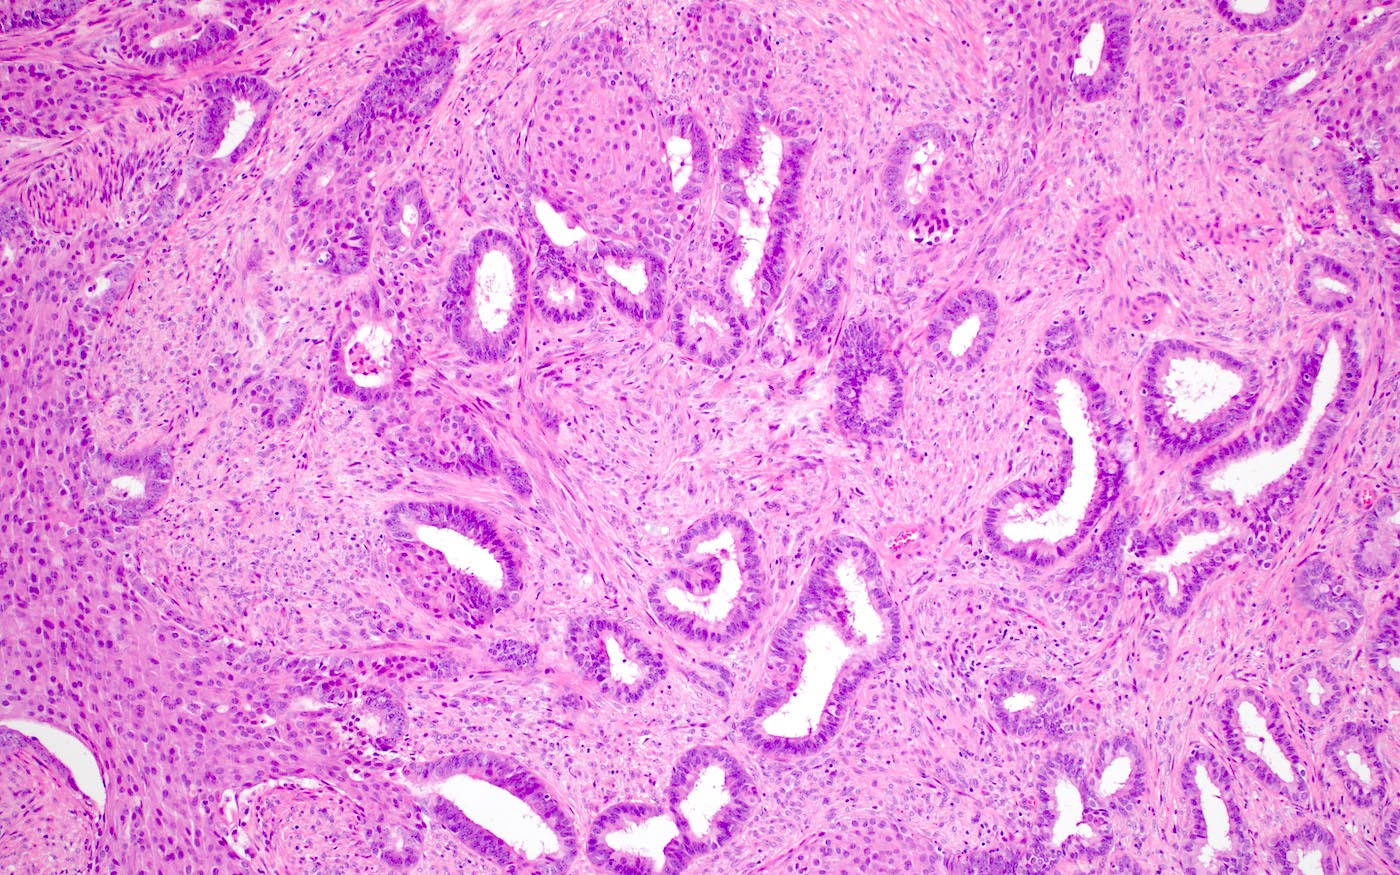

Microscopic (histologic) description

- Biphasic tumor:

- Endometrioid glands, usually with complex architecture and sometimes with cytologic atypia

- Glandular component often shows lobulated architecture

- Benign fibromyomatous stroma, rarely with myxoid change

- Squamous morular metaplasia is frequently seen and may show central necrosis

- Well circumscribed or slightly irregular margin

- Reference: Am J Surg Pathol 2015;39:1148

Microscopic (histologic) images